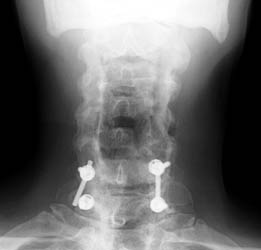

3 months later,

follow-up films show the posterior fixation at C6-7. Now noted that the

screw at C7 has slipped off the support rod on the right. |